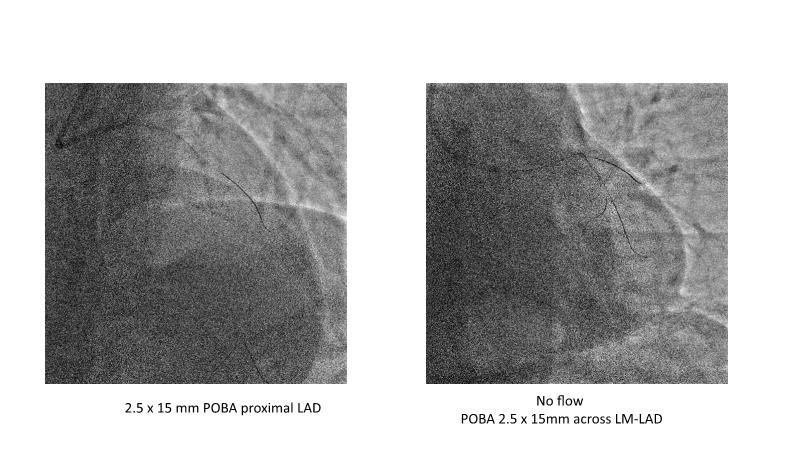

• To see advantages of RotaCUT as part of lesion preparation in left main bifurcation